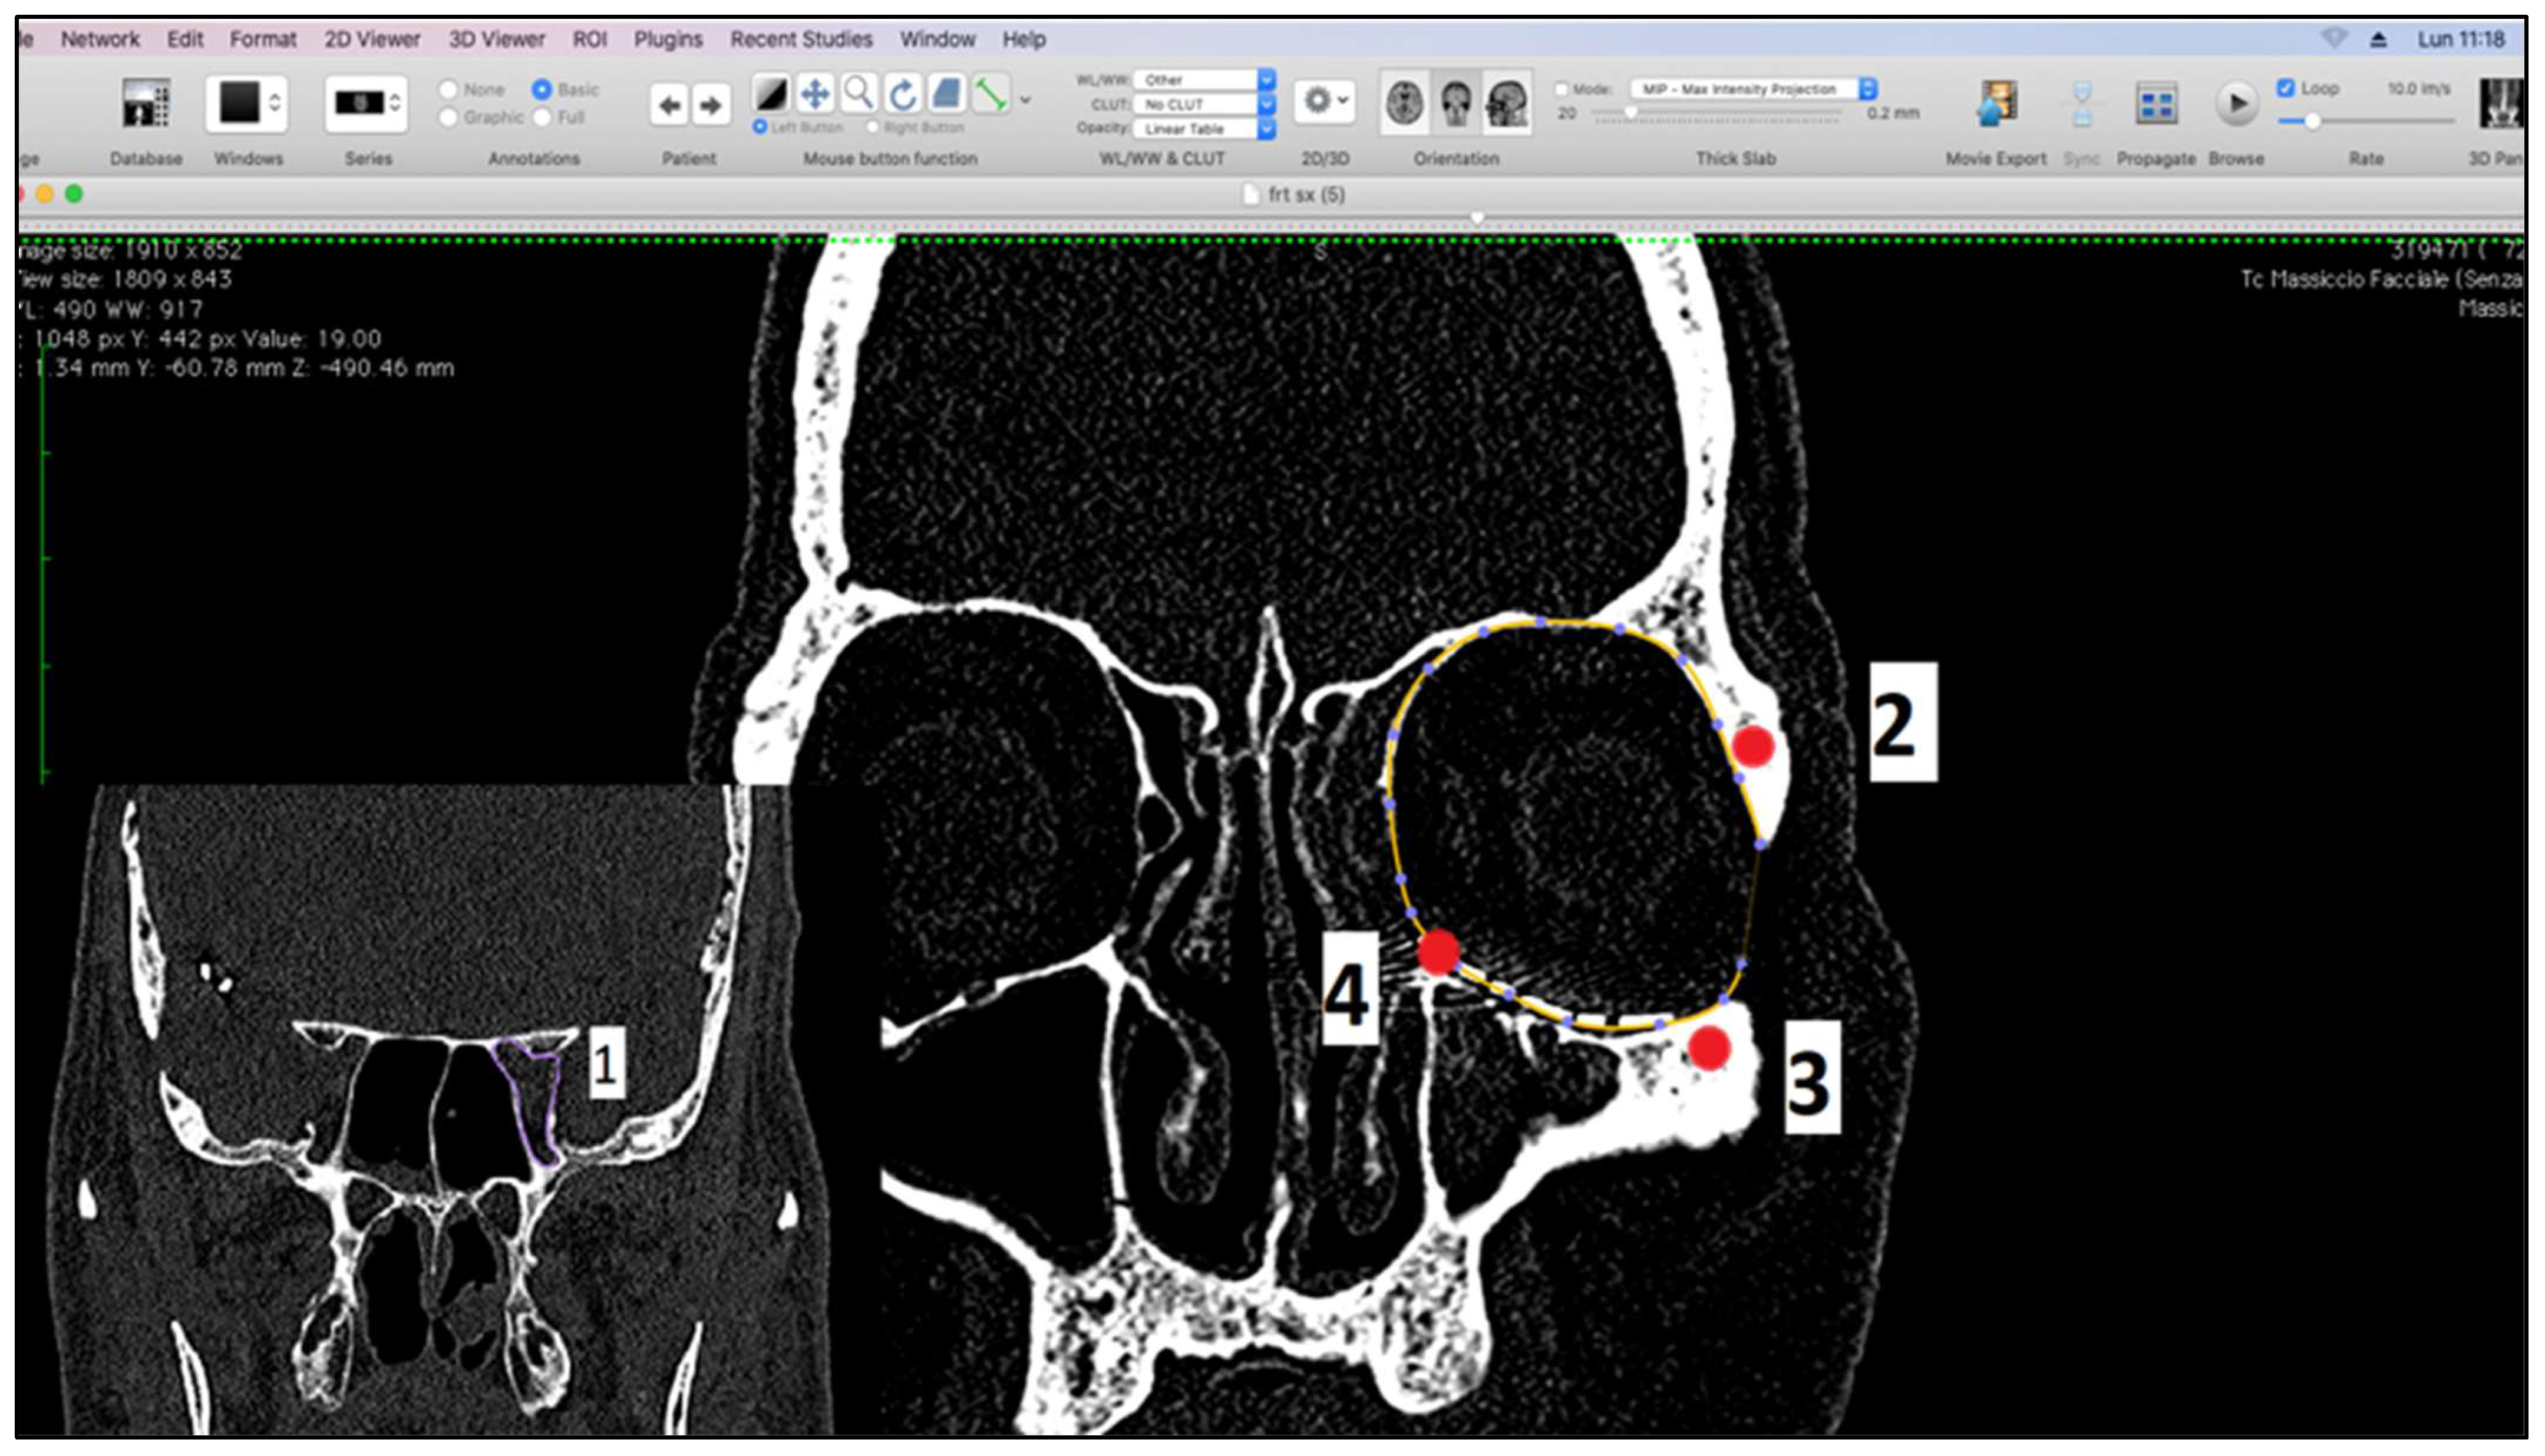

- Measurement of orbital volume using Osirix software (Version 12.0) (Pixmeo SARL, CH-1233 Bernex, Switzerland) on the new CT examination. This was carried out both semi-automatically and manually. For each patient, the orbital volume on the preoperative CT was calculated for both healthy and fractured orbits. On the postoperative CT, however, the orbital volume reconstructed with titanium mesh was calculated. We then calculated the difference in volumes between healthy and traumatized orbit, both before and after surgery. Finally, we evaluated the recovery difference, which is made up of the difference between the two volumes, pre-op and post-op, of the traumatized orbit.

2.2. Measurement of Orbital Volumes